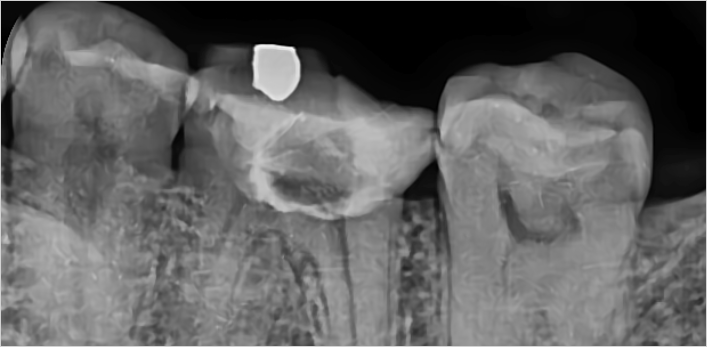

김** 환자분 (신경치료 진행 후 지르크라운으로 치료)

왼쪽아래 어금니 통증으로 방문,

보철물 제거 후 확인해보니 남은 치질이 별로 없어 post 추가 및 신경치료 진행 후 지르크라운으로 치료

위 치료 사례는 서울스마트치과에서 직접 치료를 받고, 환자 본인의 동의를 얻어 게재된 사진으로 무단 인용, 도용, 재배포 시 민/형사상 책임을 질 수 있습니다.